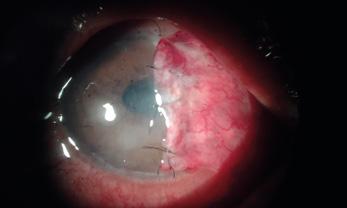

La queratitis ulcerativa periférica (QUP) es una lesión inflamatoria y destructiva del estroma y epitelio corneal yuxtalimbar que lleva a un adelgazamiento progresivo de la córnea. En su etiopatogenia están involucrados desórdenes inmunológicos favorecidos por la vasculatura perilimbar. Muchas veces cursa con escasa sintomatología, por lo que puede llegar a la perforación sin que el paciente sea consciente de ello.

La QUP puede aparecer de forma aislada o estar asociada a una enfermedad sistémica, siendo los síndromes vasculíticos los más frecuentes.

En estos casos, la QUP puede ser la primera manifestación de la enfermedad sistémica siendo la afectación ocular un signo de mal pronóstico ya que expresa actividad de la enfermedad.

La granulomatosis con poliangeitis asociada a ANCA C+ (exenfermedad de Wegener) es una vasculitis granulomatosa necrotizante sistémica, potencialmente letal, que puede afectar los tejidos oculares. En su manejo, son fundamentales el diagnóstico precoz y un tratamiento adecuado.

Paciente masculino de 48 años de edad se presenta en la guardia oftalmológica refiriendo leve dolor y molestias en el ojo izquierdo de aproximadamente 1 mes de evolución. A la anamnesis dirigida, el paciente menciona como antecedente: anemia y nefropatía en estudio.

AVMC: OD: 10/10

OI: 2/10

Bomicroscopia:

OD: inyección conjuntival mixta, úlcera corneal periférica con forma de media luna de horas 7 a 11.

OI: inyección conjuntival mixta, úlcera periférica de horas 12 a 5, con perforación a horas 3, protrusión de iris.

FO: sin particularidades en AO.

Se realiza interconsulta con reumatología y se decide intervención quirúrgica urgente de reparación primaria con parche escleral y recubrimiento conjuntival en OI, y solo recubrimiento conjuntival en OD, que se realiza el mismo día.

Luego de la cirugía, se inicia tratamiento sistémico con meprednisona 40mg/día, vía oral. El paciente presenta buena evolución a las 24 horas de postoperatorio.

En los exámenes de laboratorio solicitados por reumatología, el paciente presenta anemia, proteinuria, microhematuria, ANCA C+, diagnosticándose granulomatosis con poliangeitis asociada a ANCA C+. A los 10 días, el paciente presenta nueva úlcera corneal periférica inferior en OD, por lo que reumatología indica pulsos de metilprednisolona y posteriormente tratamiento inmunosupresor con ciclofosfamida. En los días siguientes evoluciona de forma desfavorable presentado adelgazamiento corneal periférico en AO. Se interviene nuevamente al paciente realizando recubrimiento con membrana amniótica bilateral.

En los controles presenta una evolución favorable con membrana amniótica aplicada que se reabsorbe a los 10 días –aproximadamente– en ambos ojos. Se observa franca mejoría de la superficie, transparencia, espesor e inflamación corneal.

Al mes de la última cirugía, el paciente continúa con enfermedad inactiva, asintomático y córnea en condiciones estables. Se realiza seguimiento por reumatología con tratamiento inmunosupresor mediante pulsos de ciclofosfamida.